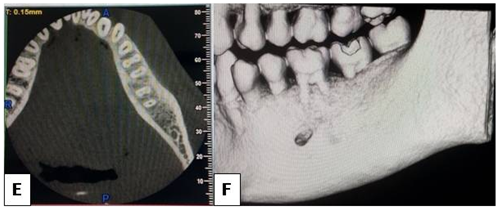

Figure 2 C- showing the extent of a well defined radiolucency in the IOPA of mandibular left back tooth region. D- showing the same on an OPG.

Figure 3 E- showing axial section of a CBCT image showing no cortical expansion. F- 3D section of the same showing horizontal bone loss and no cortcal expansion.